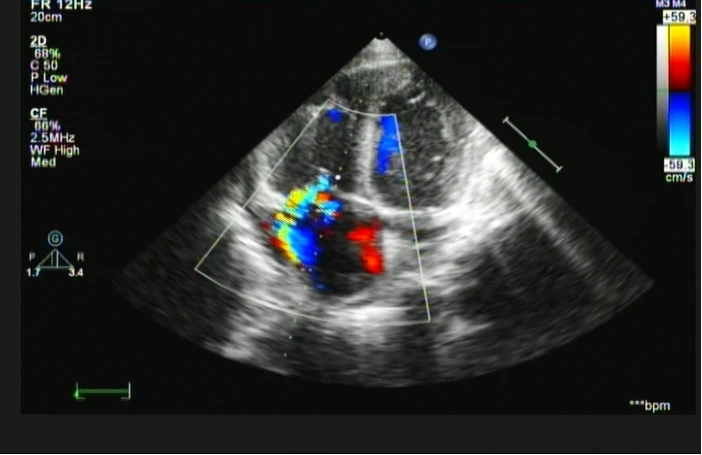

这天上午,超声心动图室来了一位24岁的年轻患者,主诉既往体健康但胸闷半月余,我看着体型微胖的小伙,心中暗忖“会不会是精神压力过大而导致的短时间身体不适感呢?”,一套常规流程下来,我的初步印象:双房增大,双室轻大;右房中等回声团,占位?(图1)三尖瓣中量偏心性花色湍流(图2)。

图1 图2